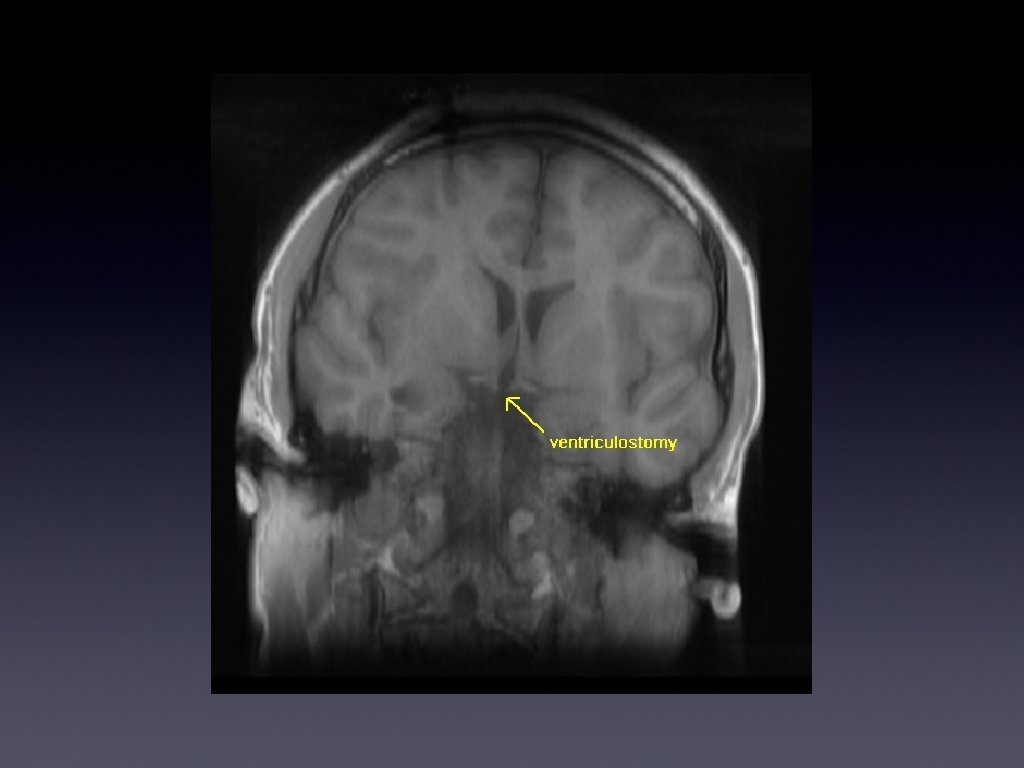

MR No enhancement or feeding/draining vessels

Benign vascular lesion and clot Consistent with cavernous malformation POD 7 - Mild LUE drift, resolved parasthesiae